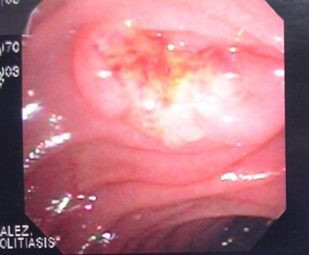

Colagiopancreatografía Retrógrada Endoscópica (ERCP)

Envíado por Gastroclínica